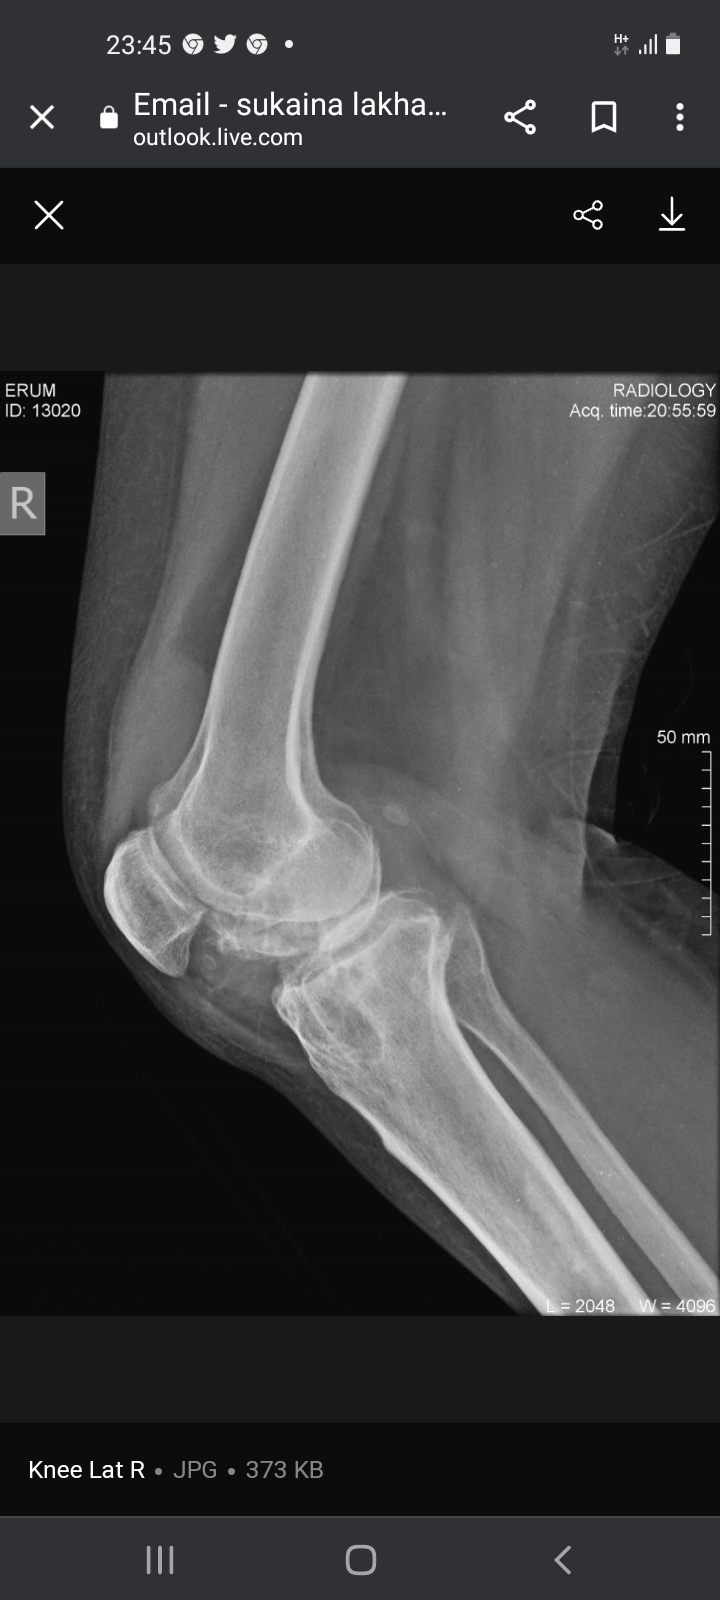

Not sure which treatment you are referring to. the Xrays show quite a bit of damage for someone who is just 40 yrs old. I suspect the patient may have inflammatory arthritis causing this. for this she should consult a qualified Rheumatologist for specialist treatment

I agree with Dr. Ashar, you are too young to have these x rays. See a rheumatologist soon.